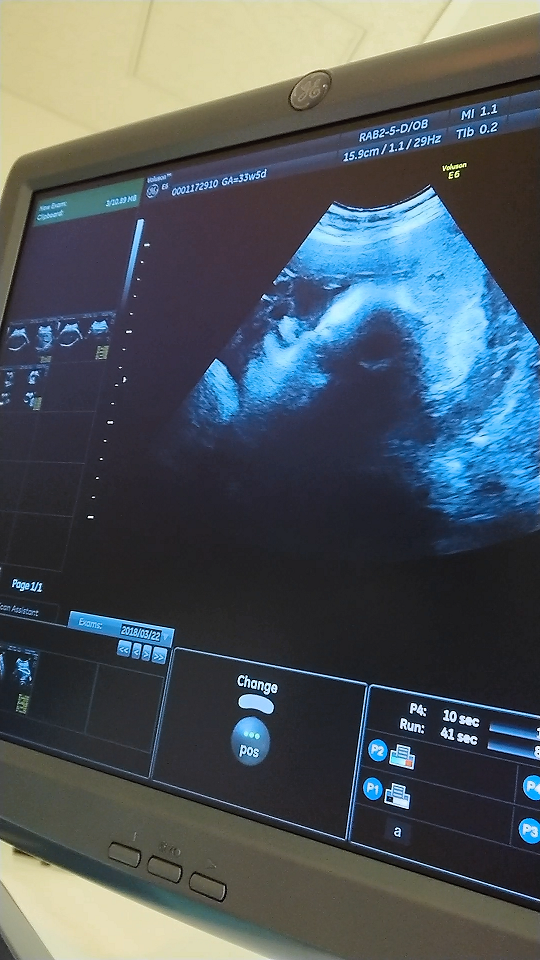

33週6日(33w6d・女の子)|あんこきなこ さん(43歳)

エコー写真撮影時のエピソード:

写真は33週6日です。

手で顔を覆っているので、写真では顔が隠れてしまってますが、この写真を撮る前は手も動いていて、口をモゴモゴする表情が見られたので、可愛いな〜と思う1枚のエコー写真です。

最近、息苦しくなってきました。お腹も少し歩くと張りやすくもなってきたようです。